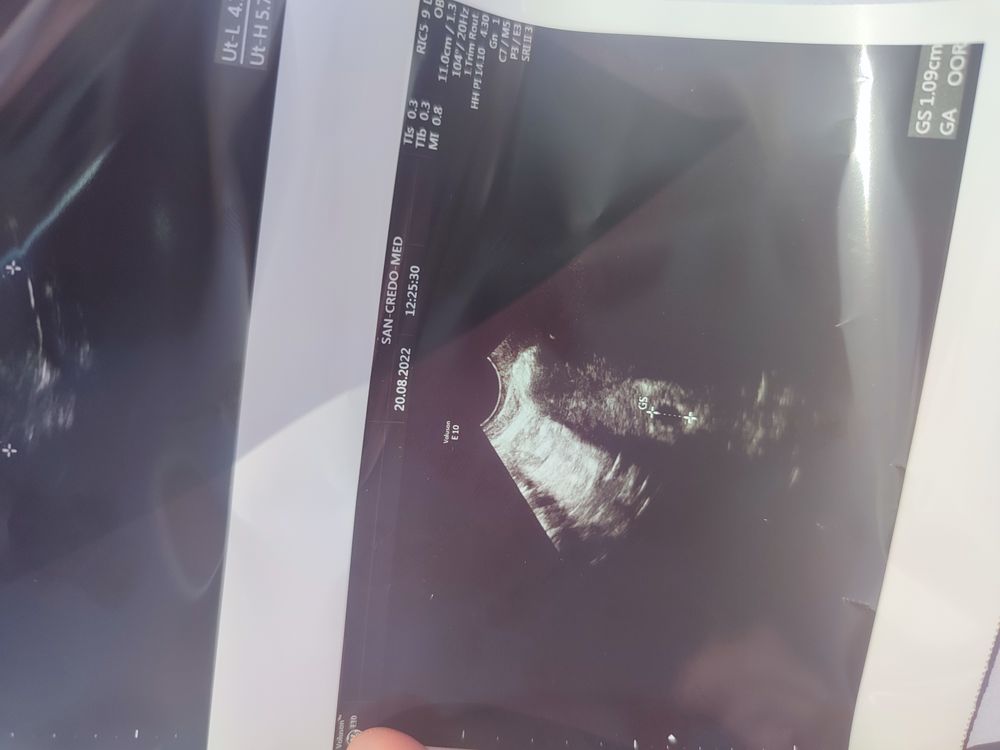

Сходила на УЗИ...

Как всегда я лох.... Убежала ничего не спросила.... Думала почитаю в заключении, а там на польском.... Вообщем позавчера пя был 2-3 мм. Сегодня на УЗИ написали 1.09 см... Я так понимаю мы выросли... И хорошо?

Позавчера измерили неправильно,при вашем хгч оно явно больше было,у меня 7 мм было,за день до УЗИ хгч был 1990,ну вот сегодня правильно померяли

Daria, да выросли конечно,пя растет примерно 1 мм в день,даже если у вас там 7 мм было,то через 2 дня 10,9 мм это прям супер рост